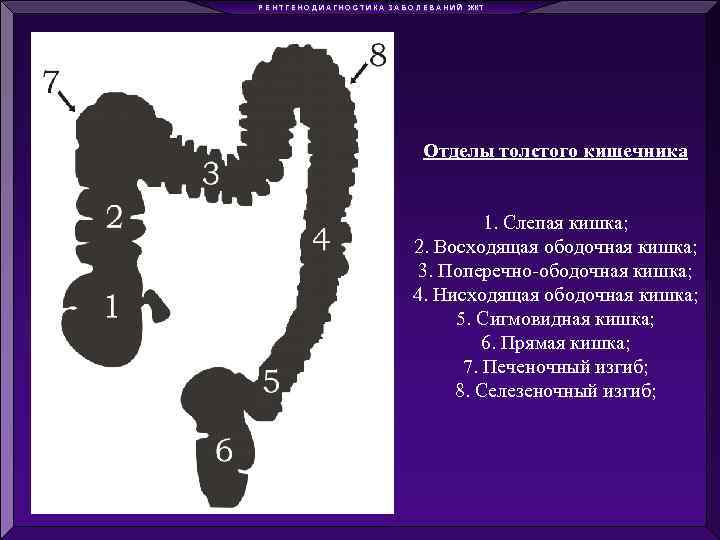

Р Е Н Т Г Е Н О Д И А Г Н О С Т И К А З А Б О Л Е В А Н И Й ЖКТ Отделы толстого кишечника 1. Слепая кишка; 2. Восходящая ободочная кишка; 3. Поперечно-ободочная кишка; 4. Нисходящая ободочная кишка; 5. Сигмовидная кишка; 6. Прямая кишка; 7. Печеночный изгиб; 8. Селезеночный изгиб;

Р Е Н Т Г Е Н О Д И А Г Н О С Т И К А З А Б О Л Е В А Н И Й ЖКТ Отделы толстого кишечника 1. Слепая кишка; 2. Восходящая ободочная кишка; 3. Поперечно-ободочная кишка; 4. Нисходящая ободочная кишка; 5. Сигмовидная кишка; 6. Прямая кишка; 7. Печеночный изгиб; 8. Селезеночный изгиб;